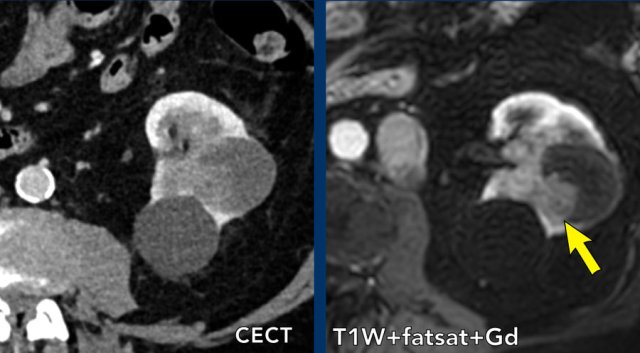

case 2

The images show a cystic mass with a thick walled (< 4mm) cyst with a few irregular thickened septa.

On the post contrast images there is no enhancement of the septa or wall but an enhancing mural nodule can clearly be identified (arrow).

This therefore represents a Bosniak IV lesion. The lesion was excised and proved to be a clear-cell carcinoma.